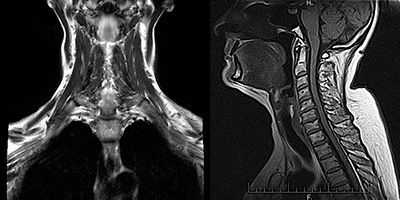

- Томография.КТ-сканирование грудной клетки выполняется для исключения патологии вилочковой железы - тимомы. Исследование имеет гораздо более высокую информативность по сравнению с традиционной рентгенографией. Высокой точностью при выявлении мягкотканных образований обладает МРТ, ее выполнение увеличивает диагностическую ценность рентгенологического метода.

Ценную информацию может дать компьютерная томография органов средостения. В силу того, что большой процент случаев миастении можно связать с объемными процессами в вилочковой железе, КТ средостения таким больным проводят достаточно часто.

Компьютерная томография средостения. Используется для исключения тимомы - опухоли вилочковой железы, которая может продуцировать антитела.